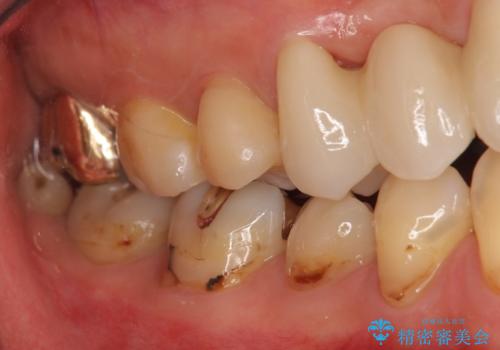

結果、非常に満足していただきました。

- 44万円 (ジルコニアクラウンスタンダード 10万円×4本 仮歯1万円×4本)費用は治療当時の料金となります

右上2番単独の支台歯では不足のため、右上12とも支台歯にしています。